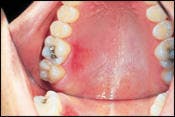

Oral examination revealed a red lesion on the hard palate of a 26-year-old male receiving routine dental treatment.

Examination of the head and neck regions revealed no unusual or significant findings. Oral examination revealed one superficial erosion on the palatal mucosa adjacent to molars. The lesion measured approximately two centimeters by one centimeter in diameter (see photo). The lesion appeared red in color. Further oral examination revealed no other oral lesions present.

Thermal burns caused by hot foods are found most often on the tissues of the hard palate and posterior buccal mucosa. Thermal burns caused by hot liquids are likely to involve the tongue and soft palate. The thermal burn typically appears as an erythematous, superficial erosion. The size and depth of the lesion vary, depending on the type of food, the temperature of the food, and the length of time the food was in contact with the oral tissues.

A superficial sloughing of the oral mucosa may be seen around the periphery of the thermal burn. The patient with a thermal burn is typically able to identify the cause of the lesion. Most thermal burns become less painful after several days and heal within one to two weeks.